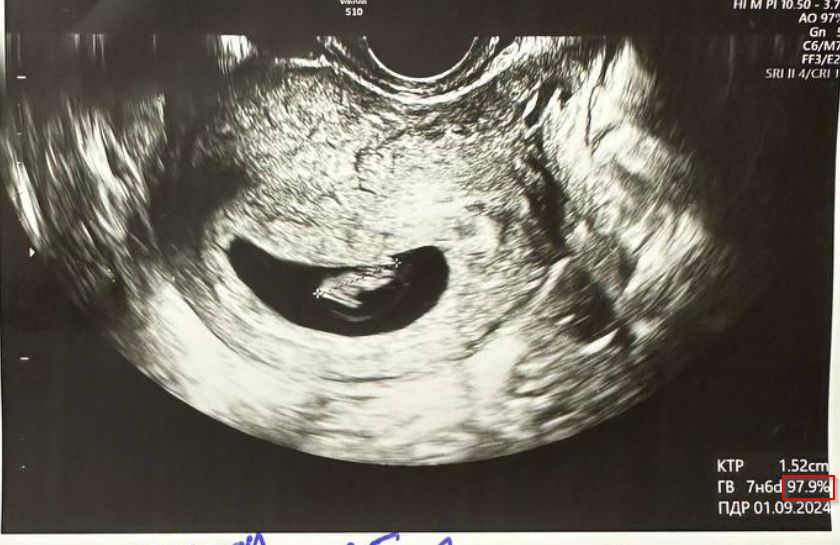

Что значит этот % на узи?

УЗИ, КТГ, доплерВсё изучаю и кручу в руках узи, наткнулась на новый для меня показатель.

Что значит этот %? На снимках обвела красным.

Скорее всего процентиль для этого срока. От 10 до 90 это хорошо